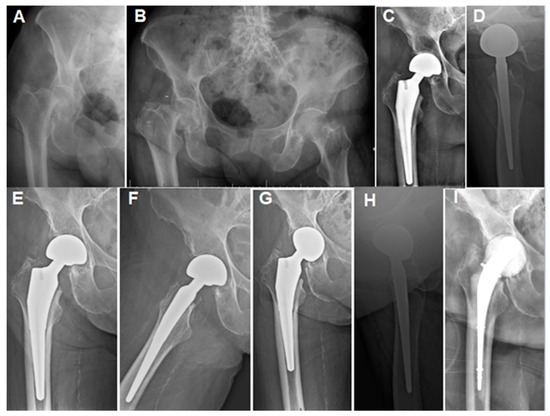

| 4: 93.2 y old (Figure 3) | CKD |

|

| Antibiotic spacer and chronic antibiotic therapy (6 weeks of IV Ertapenem 1 gm daily). | Patient maintained follow-up for 9 months after spacer insertion with wound healing, and then was lost to follow-up. |